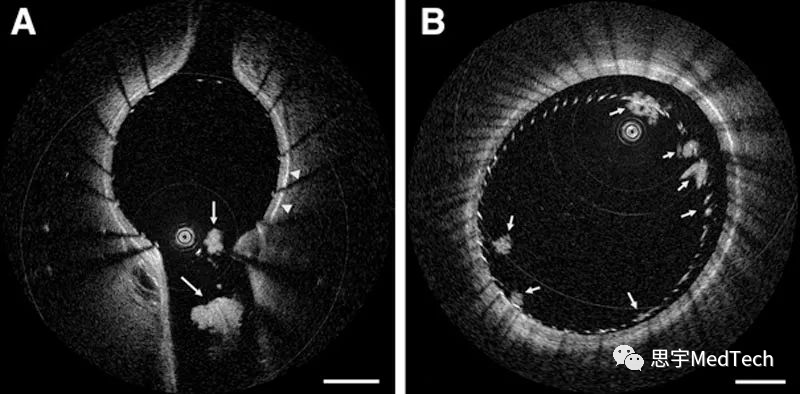

▲使用HF-OCT观察植入后的脑血管支架(猪模型);(A)植入开孔激光切割镍钛合金支架,箭头所示处存在多个血栓;(B)植入密网支架,在11点至4点箭头处可见其贴壁不良,并存在部分血凝块